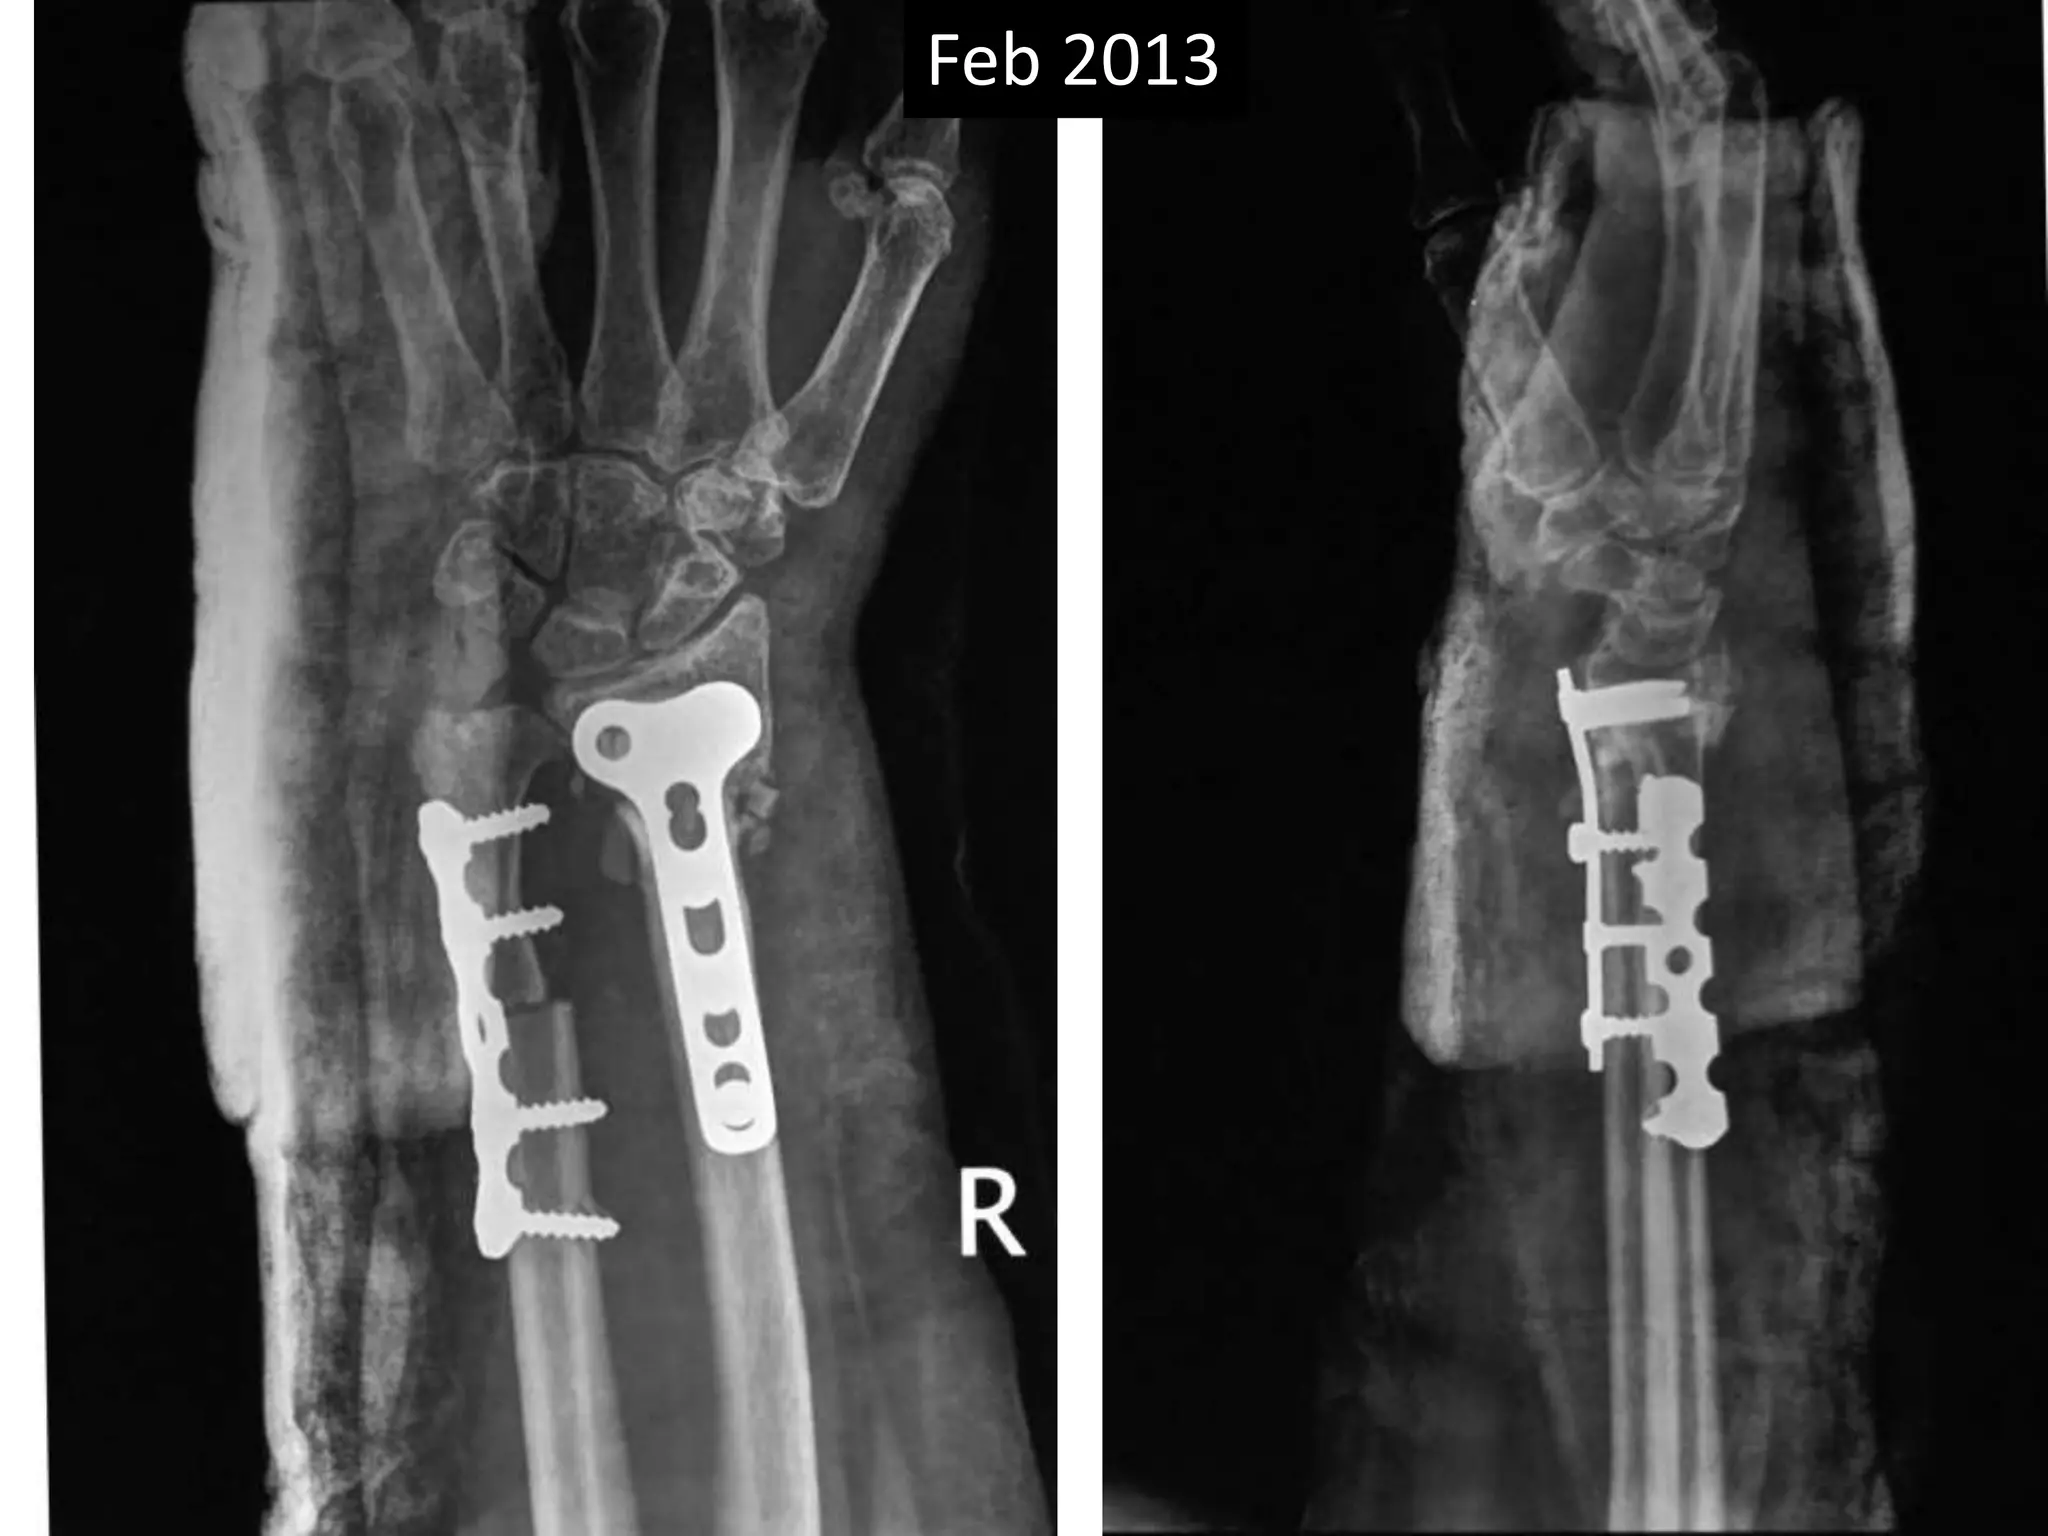

Feb 2013

April 2014

Sept 2013

Case two

• 50 years old female

• Low energy injury

• Sustained fracture lower end radius

• Pop cast for six weeks

• Progressively increasing deformity following

removal of plaster.

• X- rays after six months following fracture

showing non-union.

Surgery

• Volar exposure

• Removal of scar tissue and clearing of bone

ends.

• Release of soft tissue contractures.

• Shortening of ulna and plating.

• Plating of radius with bone grafting.